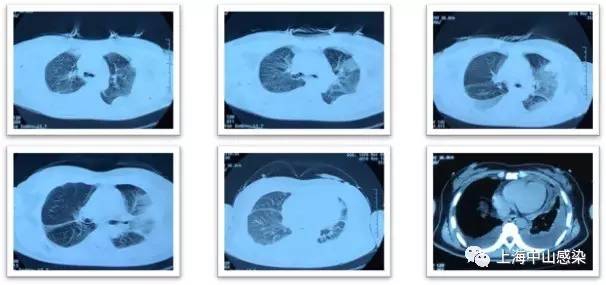

6月14日复查胸部CT2:肺炎稍吸收,但双侧胸腔积液更加明显

肺吸虫血清抗体阳性,诊为肺吸虫病,吡 喹酮1g(200mg*5片),tid,3天,8.29 CT3复查病灶明显吸收。